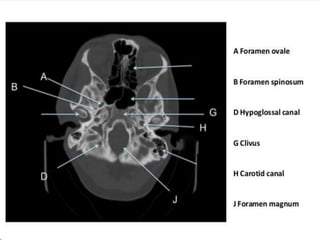

Sphenoid

sinus

Medulla

oblongata

cerebellum

4 Fourth ventricle

5 Middle cerebellar

peduncle

6 Sigmoid sinus

7 Petrous temporal

bone and mastoid

air cells

8 Cerebellopontine

angle

9 Pons

10 Pituitary fossa

11 Cerebellar

vermis

12 Basilar artery

13 Prepontine

cistern

14 Dorsum sellae

15 Temporal horn

of lateral

ventricle

16 Ambient

17

Interpeduncular

18 Cerebral

19 Sylvian

fissure

20 Supra

vermian